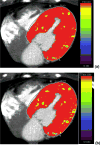

A healthy, functional microcirculation in combination with nonobstructed epicardial coronary arteries is the prerequisite of normal myocardial perfusion. Quantitative assessment in myocardial perfusion and determination of absolute myocardial blood flow can be achieved noninvasively using dynamic imaging with multiple imaging modalities. Extensive evidence supports the clinical value of noninvasively assessing indices of coronary flow for diagnosing coronary microvascular dysfunction; in certain diseases, the degree of coronary microvascular impairment carries important prognostic relevance. Although, currently positron emission tomography is the most commonly used tool for the quantification of myocardial blood flow, other modalities, including single-photon emission computed tomography, computed tomography, magnetic resonance imaging, and myocardial contrast echocardiography, have emerged as techniques with great promise for determination of coronary microvascular dysfunction. The following review will describe basic concepts of coronary and microvascular physiology, review available modalities for dynamic imaging for quantitative assessment of coronary perfusion and myocardial blood flow, and discuss their application in distinct forms of coronary microvascular dysfunction.